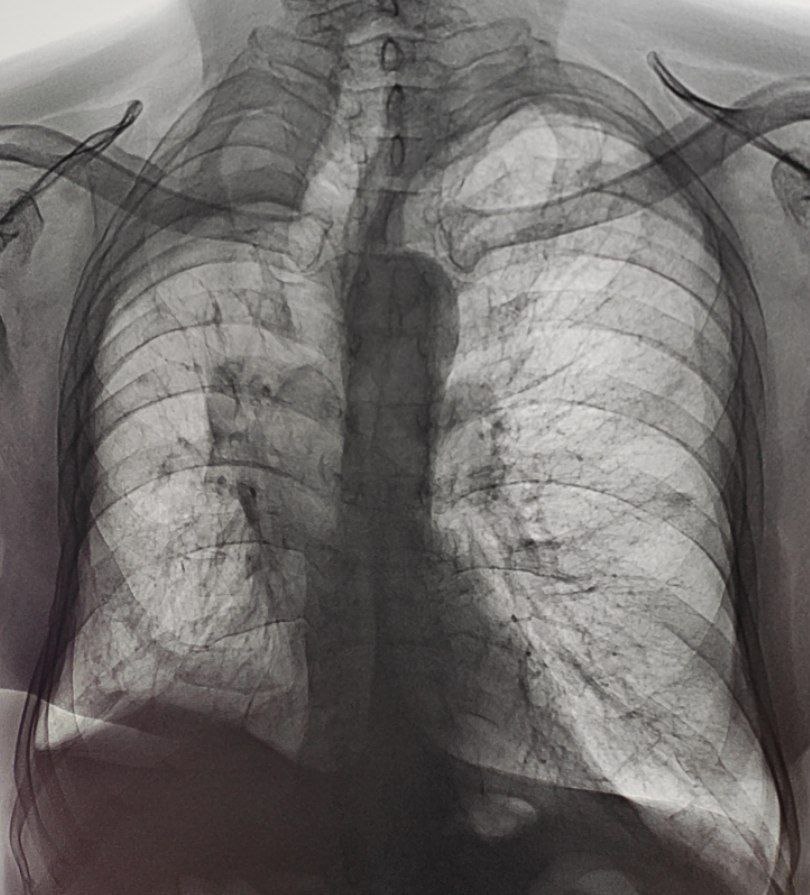

Тоже ради интереса. Точно не помню, но молодой парень, попал под поезд в 2008 г, сделали операцию.

источник

И такой красивый он пришёл уже около полугода назад

Dimon in Radiology/Рентгенология Чатоид

У кого какие идеи?🤔

ФКТ , гигантская каверна? Мелочаговая дисс.? Анамнез, архив